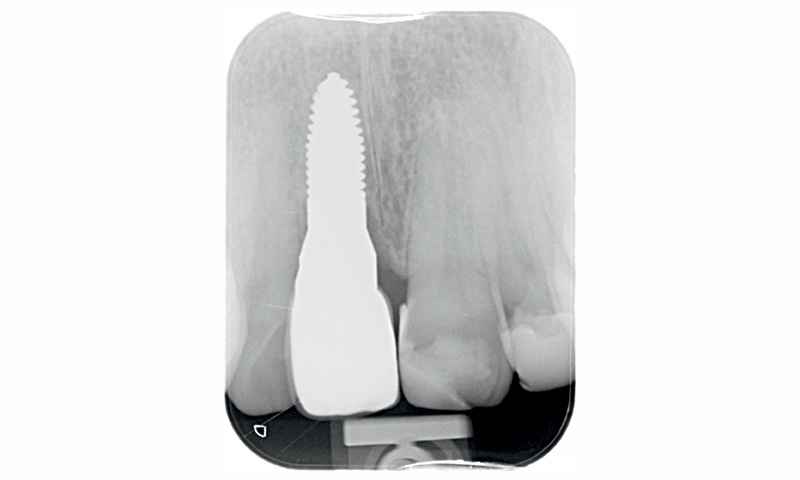

Fig. 17 (caso 3) - Radiografia 5 anni dopo l'inserimento dell'impianto. Marginal bone loss (MBL) 0 1.24 mm